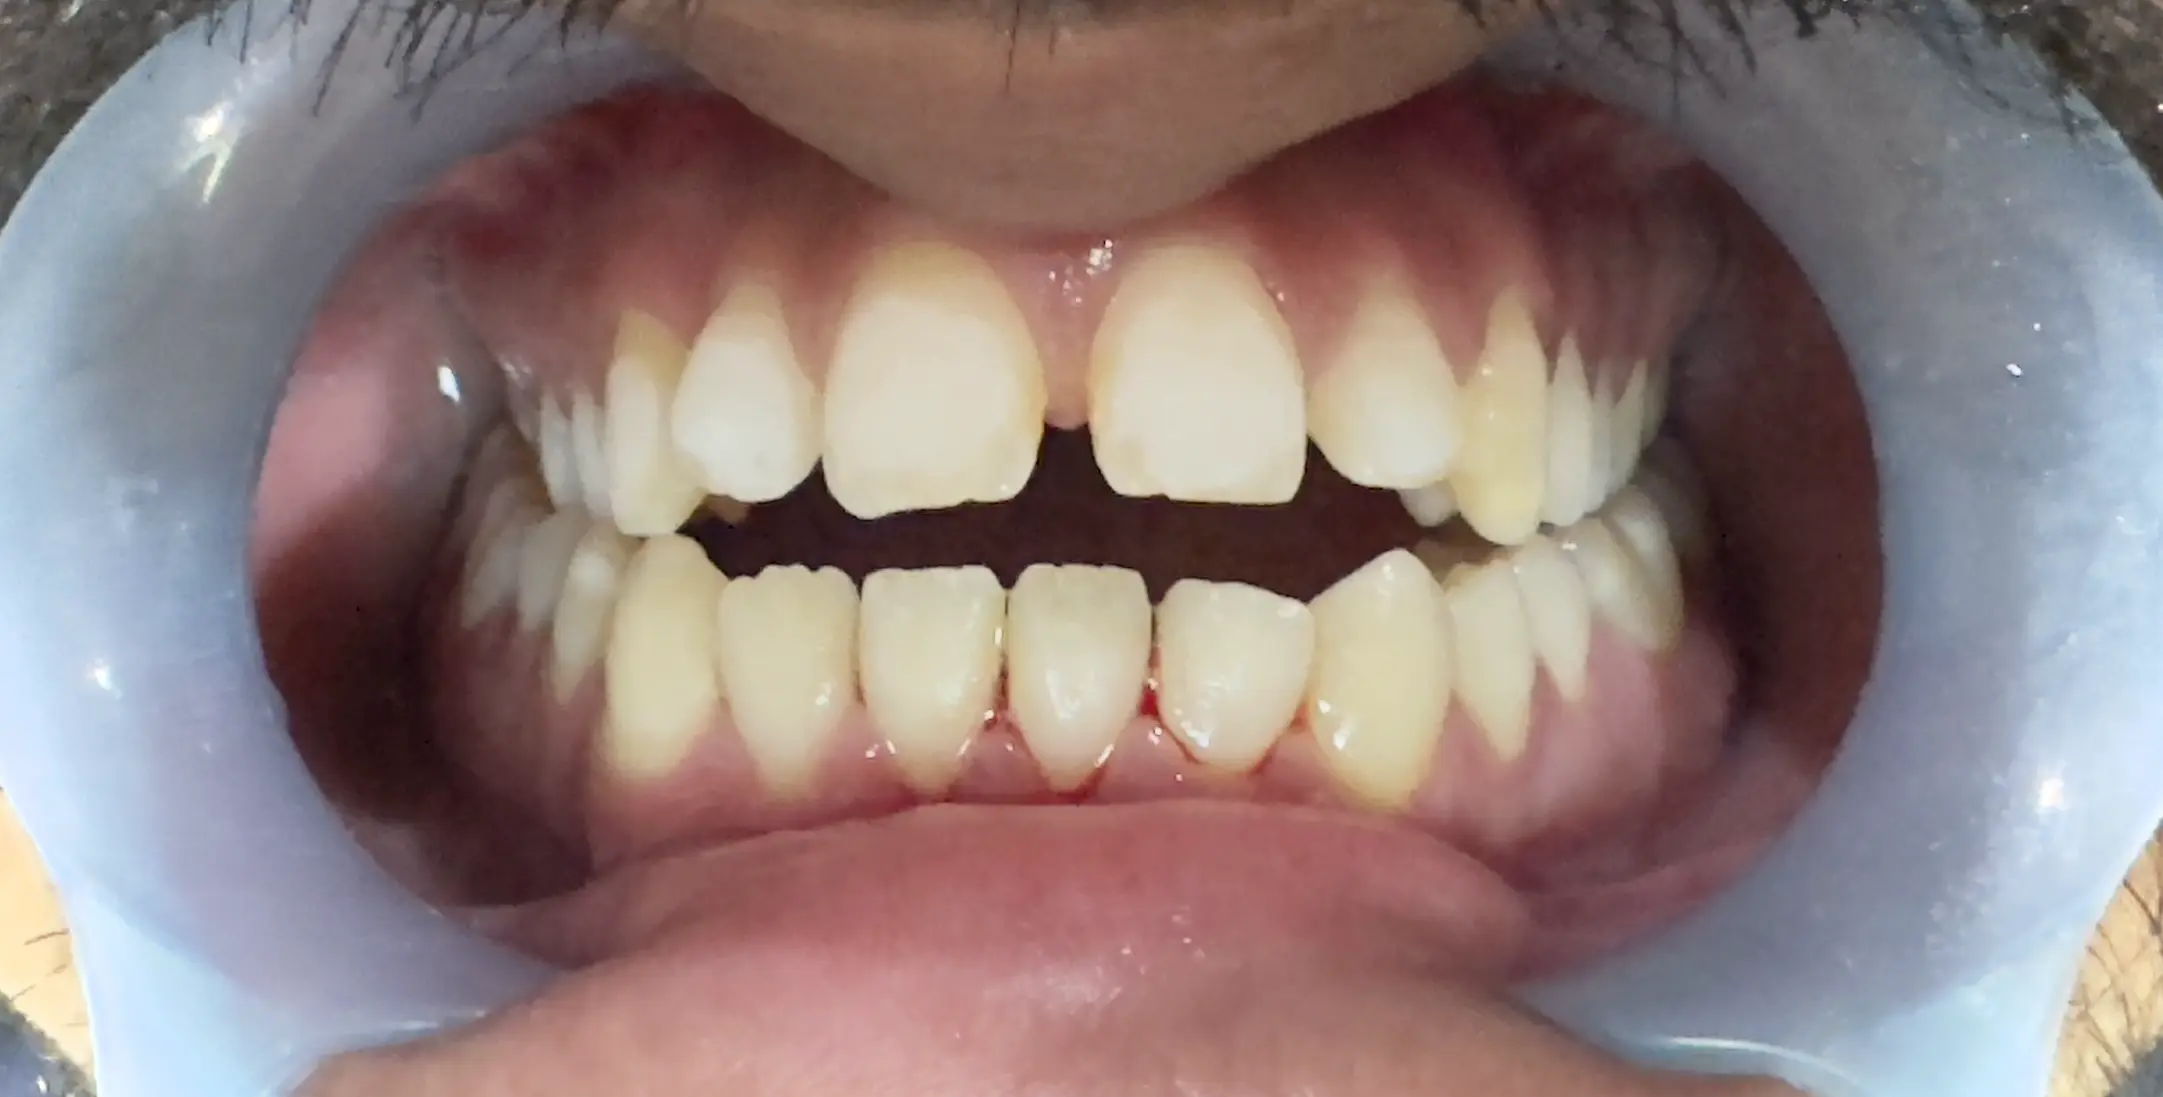

Have you ever wondered what is the solution of gaps between teeth and you are considering braces for teeth, one of the first questions that comes to mind is: Which type of braces is best for me and how much will it cost? Orthodontic treatment is not only about straightening teeth — it’s about improving bite function, oral health, and long-term confidence.

While many people seek braces for teeth for cosmetic improvement, the benefits go far beyond aesthetics. Properly aligned teeth are easier to clean, reduce the risk of gum disease, prevent abnormal tooth wear, and improve chewing efficiency.

Types of Braces for Teeth

Orthodontics has evolved dramatically over the past decade. Today, patients can choose from multiple systems designed for different needs and preferences.